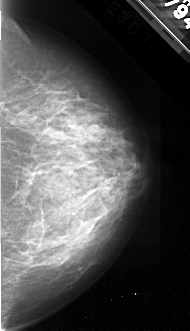

A_1097_1.RIGHT_CC

RIGHT_CC LINES 4291 PIXELS_PER_LINE 2461 BITS_PER_PIXEL 16 RESOLUTION 42 NON_OVERLAY